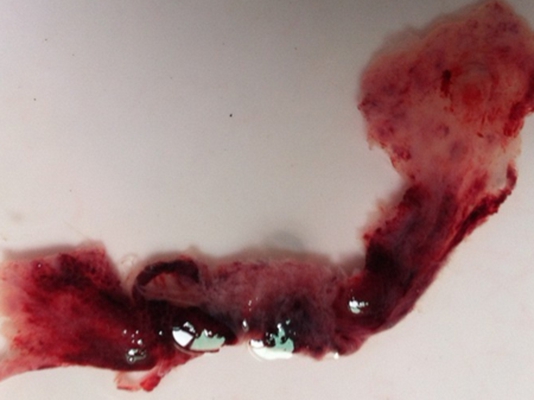

流產圖片

流產掉下來的孕囊

流產掉下來的孕囊

流產掉下來的孕囊

流產掉下來的孕囊

流產掉下來的孕囊

流產掉下來的孕囊

流產掉下來的孕囊

流產掉下來的孕囊

流產掉下來的孕囊

流產掉下來的孕囊